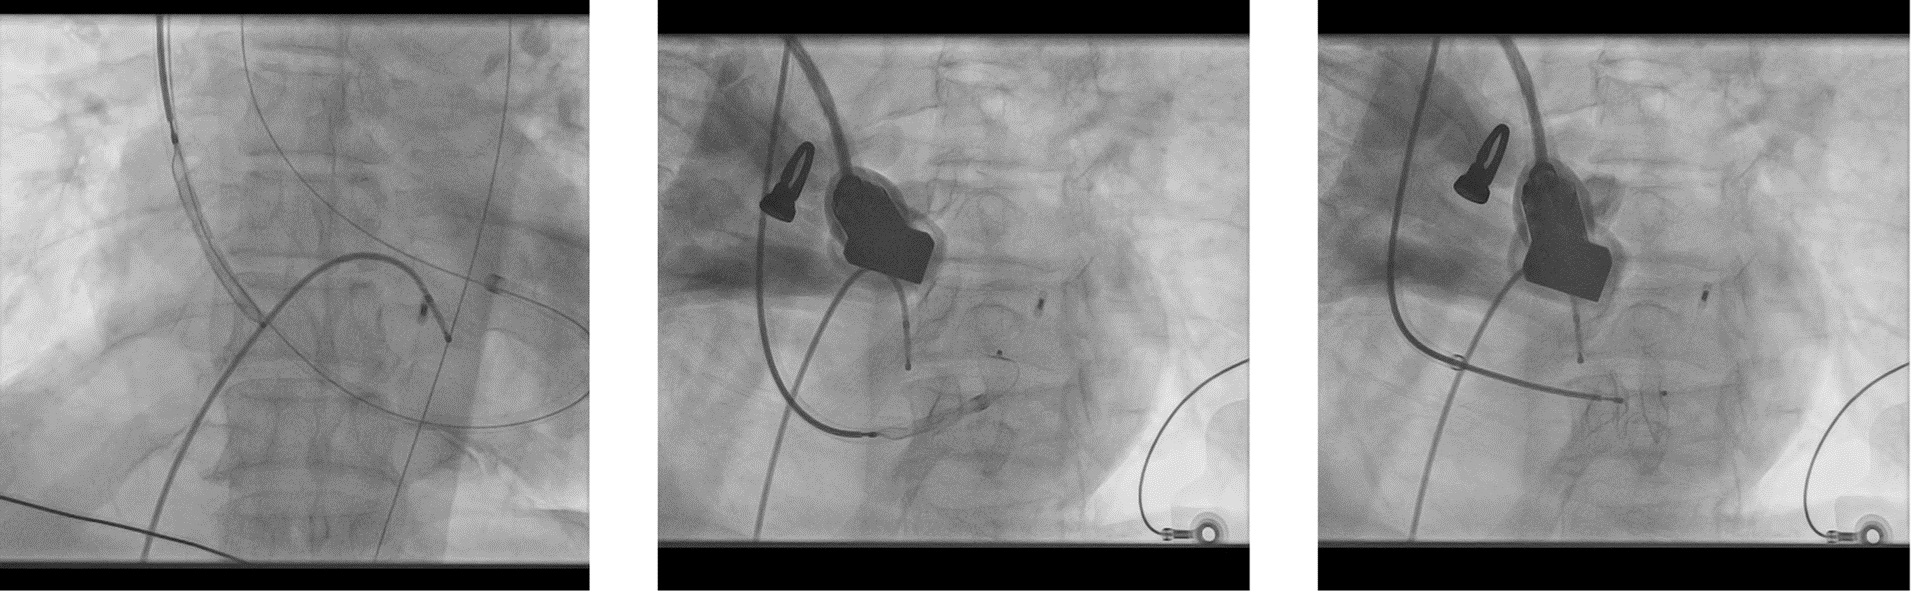

A 65-year-old hypertensive, diabetic male presented with acute anterior wall MI (window 72 hrs) complicated by cardiogenic shock and apical ventricular septal defect (VSD) on echocardiography, showing a significant left-to-right shunt with severe PAH and EF 35%. An intra-aortic balloon pump (IABP) was inserted for hemodynamic stabilization. The procedure was performed via dual access — 6F femoral arterial sheath and 8F internal jugular venous sheath. The left ventricle was cannulated, and the VSD was carefully crossed using a catheter and guidewire, which was advanced into the pulmonary artery. The wire was then snared through the VSD defect to establish an arteriovenous loop, providing stability for device delivery. Over this loop, an Amplatzer 14 mm ASD device was advanced through the 8F sheath and positioned across the apical VSD under echocardiographic and fluoroscopic guidance. After confirming proper alignment and stability, the device was successfully released, achieving complete closure of the shunt. Immediate echocardiography confirmed no residual flow across the septum. The patient was transferred to the CCU for monitoring, with gradual IABP weaning over 4–5 days. Follow-up echocardiography before discharge showed no residual shunt, improved hemodynamics, and stable LV function.

We conclude from this study that VSD device closureinsetting of Post MI is feasible and can be successful las an alternative tosurgery. In Extreme cases of hemodynamic instability and shock patient can betaken on MCS like ECMO. In our case we stabilized the patient with IABP supportand an NIV support. Although the most important risk factor for mortality ispresence of cardiogenic shock and closure in acute phase. We did our case at 72hrs. and patient was in cardiogenic shock. We used ASD device in this case asthere was adequate